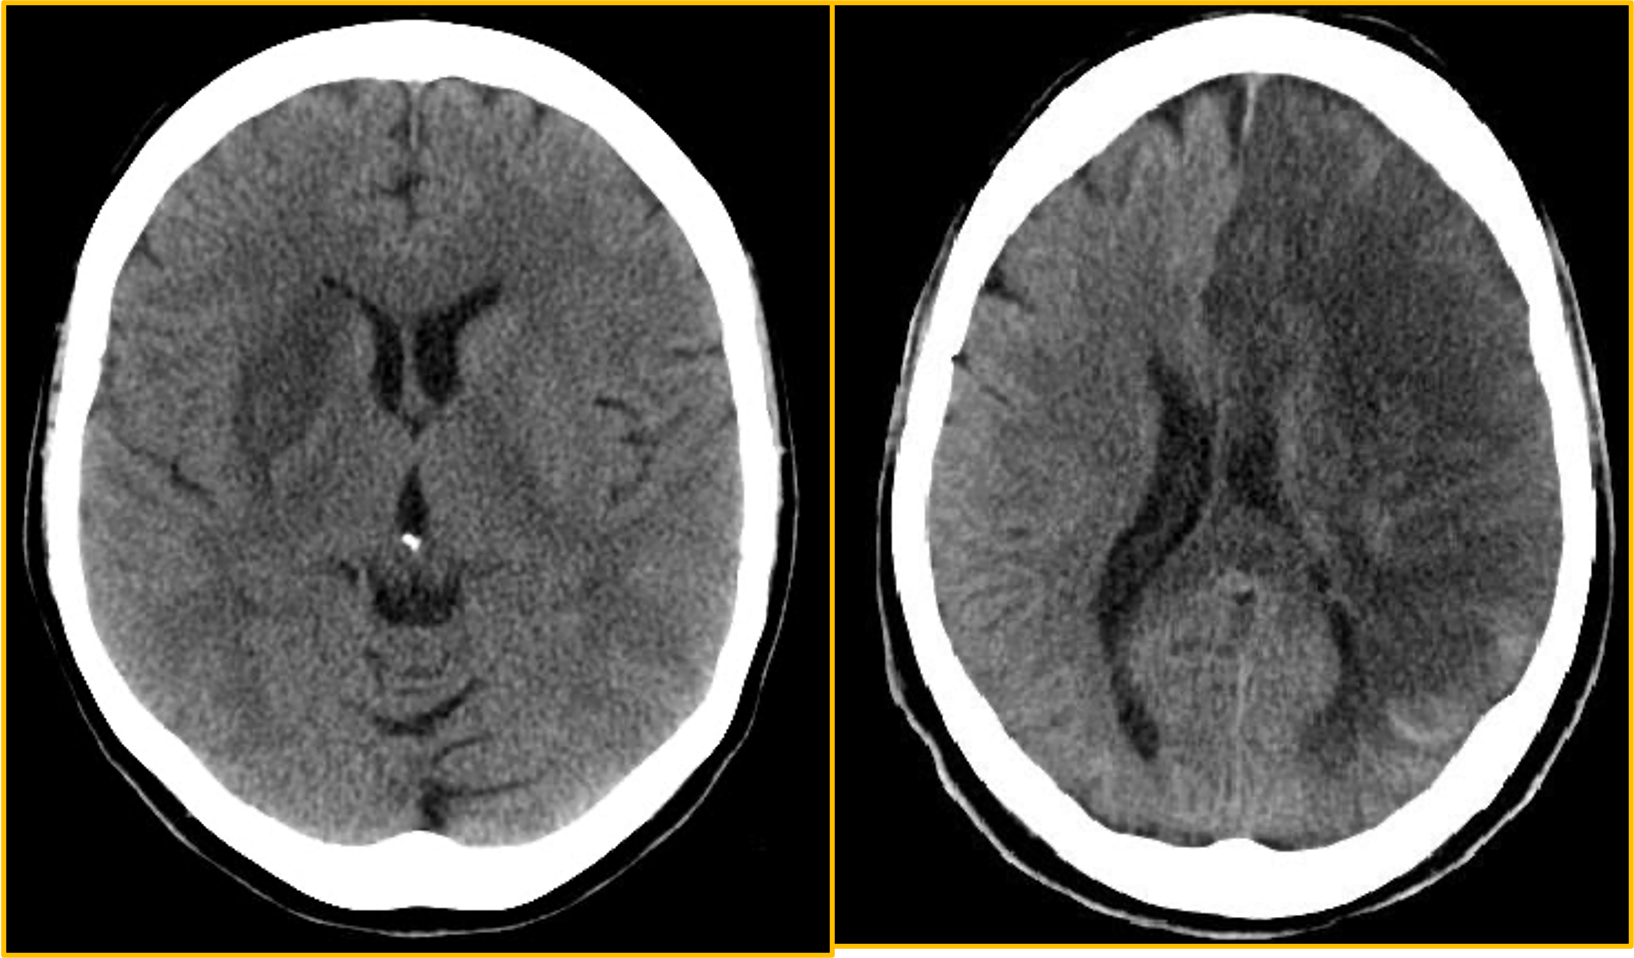

CT Examination

Axial non-contrast computed tomography (NCCT) scan demonstrates diffuse hypodensity in the right lentiform nucleus with mass effect upon the frontal horn of the right lateral ventricle in a 70-year-old woman with a history of left-sided weakness for several hours.

NCCT scan in a 52-year-old man with a history of worsening right-sided weakness and aphasia demonstrates diffuse hypodensity and sulcal effacement with mass effect involving the left anterior and middle cerebral artery territories consistent with acute infarction. There are scattered curvilinear areas of hyperdensity noted suggestive of developing petechial hemorrhage in this large area of infarction.